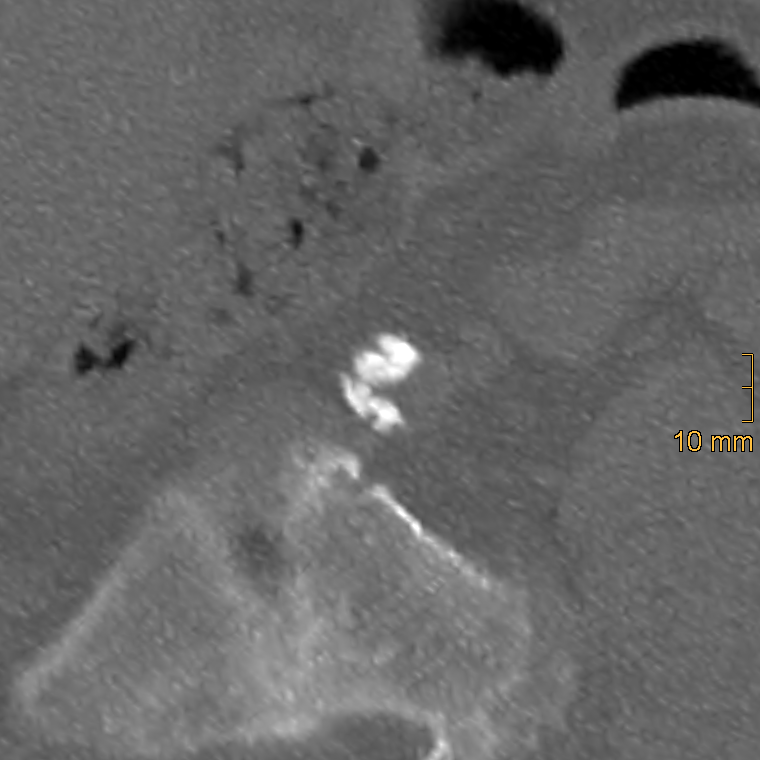

2.2.2. Iliac Artery Calcification